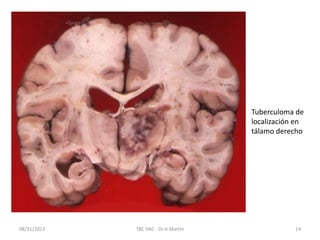

08/31/2013 TBC SNC - Dr.H.Martín 13

Tuberculoma Aislado en

paciente con Meningitis

Tuberculosa

CAT No contrastado

mostrando hidrocéfalo

comunicante típico en el

Estadio II de la Meningitis

Tuberculoma en RMN

08/31/2013 TBC SNC- Dr.H.Martín 13 Tuberculoma Aislado en paciente con Meningitis Tuberculosa CAT No contrastado mostrando hidrocéfalo comunicante típico en el Estadio II de la Meningitis tuberculosa Tuberculoma en RMN